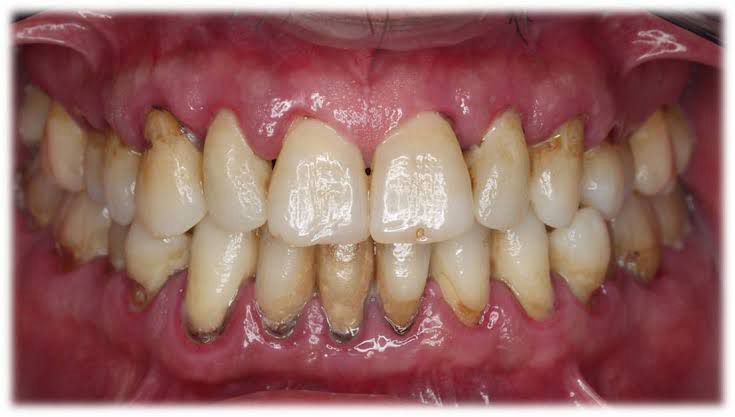

La periodontitis o piorrea es la consecuencia de una gingivitis que no ha sido tratada a tiempo. Causa una fuerte inflamación de los tejidos que soportan los dientes (encía, hueso, ligamento periodontal y cemento), movilidad ( aflojamiento de las piezas) y pérdida del hueso que rodea los dientes. Se trata de un problema grave y crónico que requiere seguimiento por parte de un especialista y un tratamiento adaptado a las circunstancias particulares del paciente.

Ésta es una patología que genera inflamación, sangrado e irritación de las encías. Si se trata a tiempo, es reversible. Pero si no recurres a un tratamiento especializado, esta enfermedad puede generar problemas mucho más graves, como la periodontitis.

La principal causa es la acumulación y reproducción de bacterias sobre las piezas dentales y la encía. Mantener unos buenos hábitos de higiene y asistir a las limpiezas dentales periódicas, es la mejor opción para controlarla.